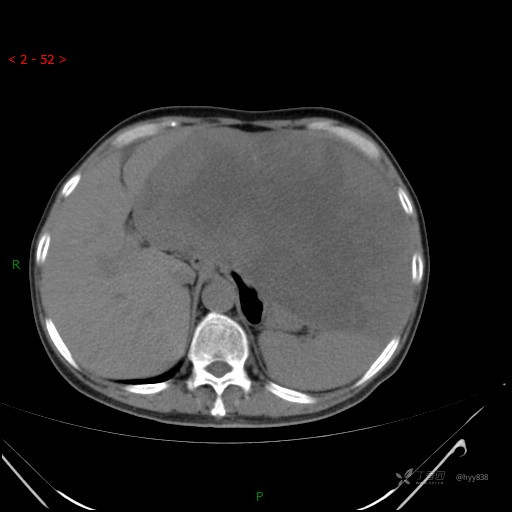

增强动脉期